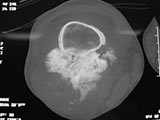

- Lobulated and ossified exophytic mass (cauliflower-like) adjacent to the cortex; attached to metaphyseal cortex via a broad base

- Centrally, the tumor is radiodense (demonstrates ossification)

- Peripherally there may be small radiolucies that represent low grade cartilaginous lobules, fibrous tissue or fat

- The underlying cortex may be thickened

- There is no periosteal reaction since the tumor comes from the outer layer of the periosteum and therefore does not elevate the periosteum.

- Appears to have broad attachment to underlying cortex with a cleft between exophytic base and cortex at periphery. This is referred to as a “String Sign” (cleft is often only identifiable on CT scan)

- There may be invasion of the medullary canal with long standing disease